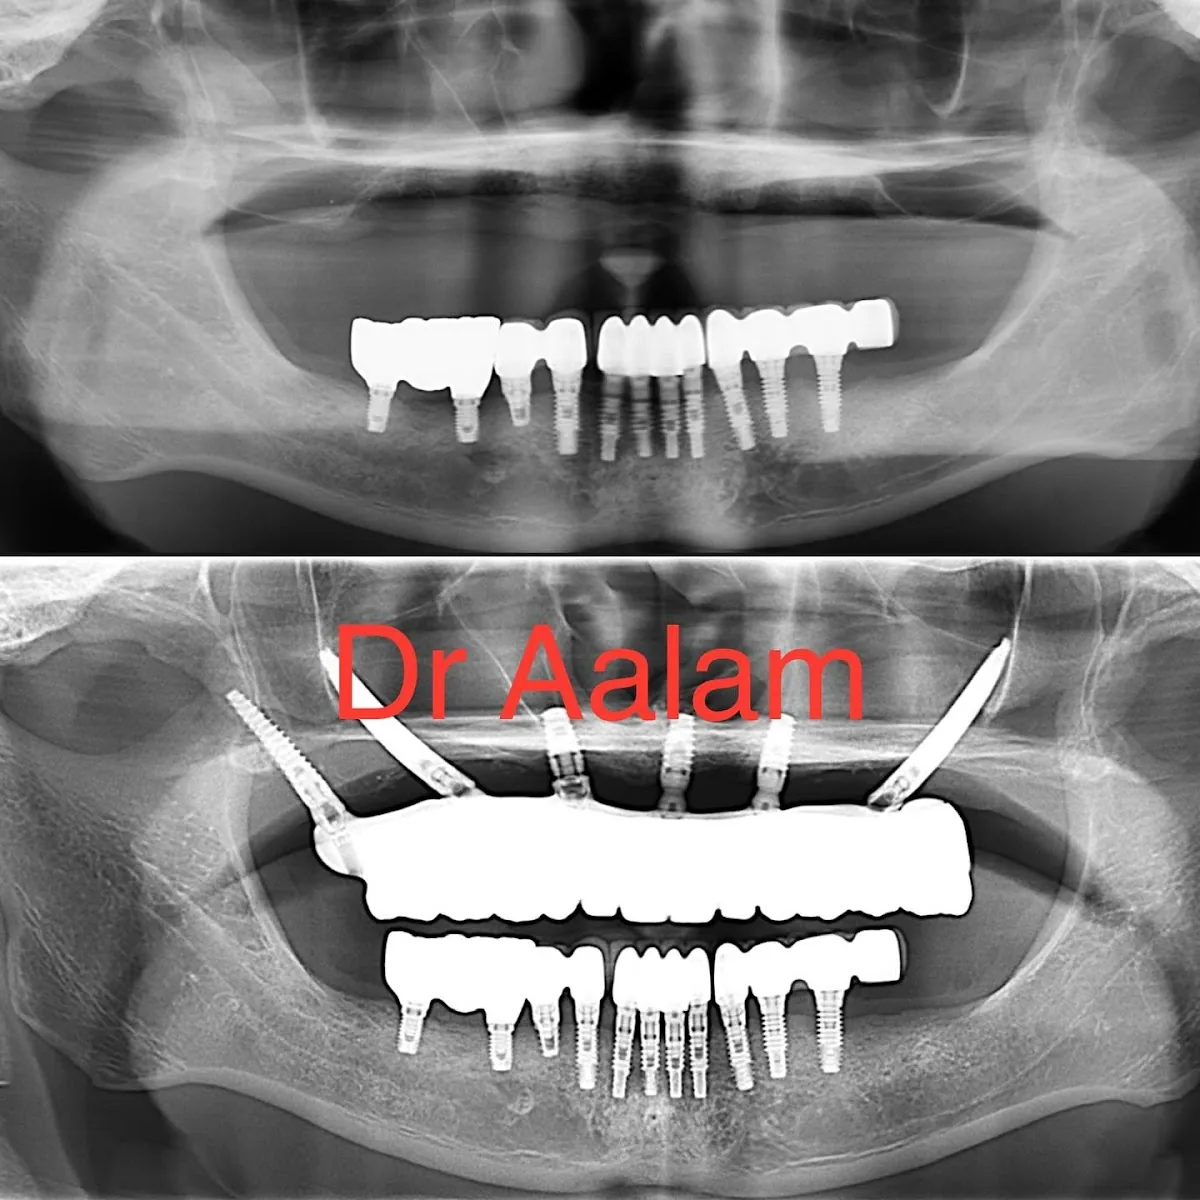

Board-certified periodontists and USC faculty specializing in complex dental implants and bone grafting

Dental Implants, Periodontics, Bone Grafting, APRF Therapy

Complex implant cases, Full-arch reconstruction, Bone grafting, Gum disease treatment

Patients needing complex implant surgery, Full-mouth reconstruction candidates, Cases requiring bone grafting